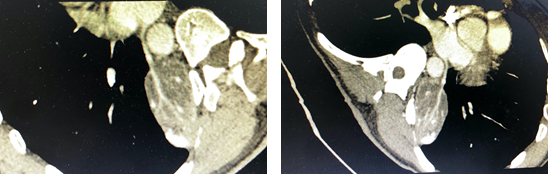

肺隔离症为先天性发育异常的肺疾病,其主要特点是病变由体动脉供血并与正常肺组织分离[1-3] 。最常见的血液供应来源于胸主动脉,其次为腹主动脉、肋间动脉、肾动脉、无名动脉、锁骨下动脉等[4]。发病率约占先天肺的发育畸形的0.2%~6.4% [5]。临床表现为非特异性,大多到合并呼吸道感染时才有症状,表现为反复肺部感染、痰血或咯血。根据解剖可以分为叶内和叶外两型。叶内型相对常见,分离的肺组织位于脏层胸膜内,很少合并其他部位畸形,多是先天性肺发育异常及后天慢性肺部感染形成,支气管与正常肺组织多相通,且静脉回流进入肺静脉,由于供血的体循环与肺循环压力差较大,从而出现反复肺部感染、咯血或痰中带血,进而形成肺纤维化、肺囊性变[6-7],推荐手术治疗;叶外型相对少见,具有独立的胸膜包裹,位于正常肺组织之外。常伴随先天性膈疝、肺气肿、支气管囊肿、先天性囊性腺瘤样畸形、先天性食管气管瘘、异位胰腺、先天性心脏病、结肠畸形等发育异常[8]。部叶外型可无症状,常在体检时发现,可随访观察,当症状进展再行手术治疗。DSA是诊断的“金标准”,增强CT或CTA是目前可以替代DSA的首选方法[9] 。

本例患者属叶外型,由左心房供血,较为罕见。

肺隔离症方面:肺隔离症虽非常见病但也非罕见。对于下叶后 基底段贴近横膈及心影旁的囊性肿块或边缘光滑的团块状阴影,均应考虑到本病的可能。